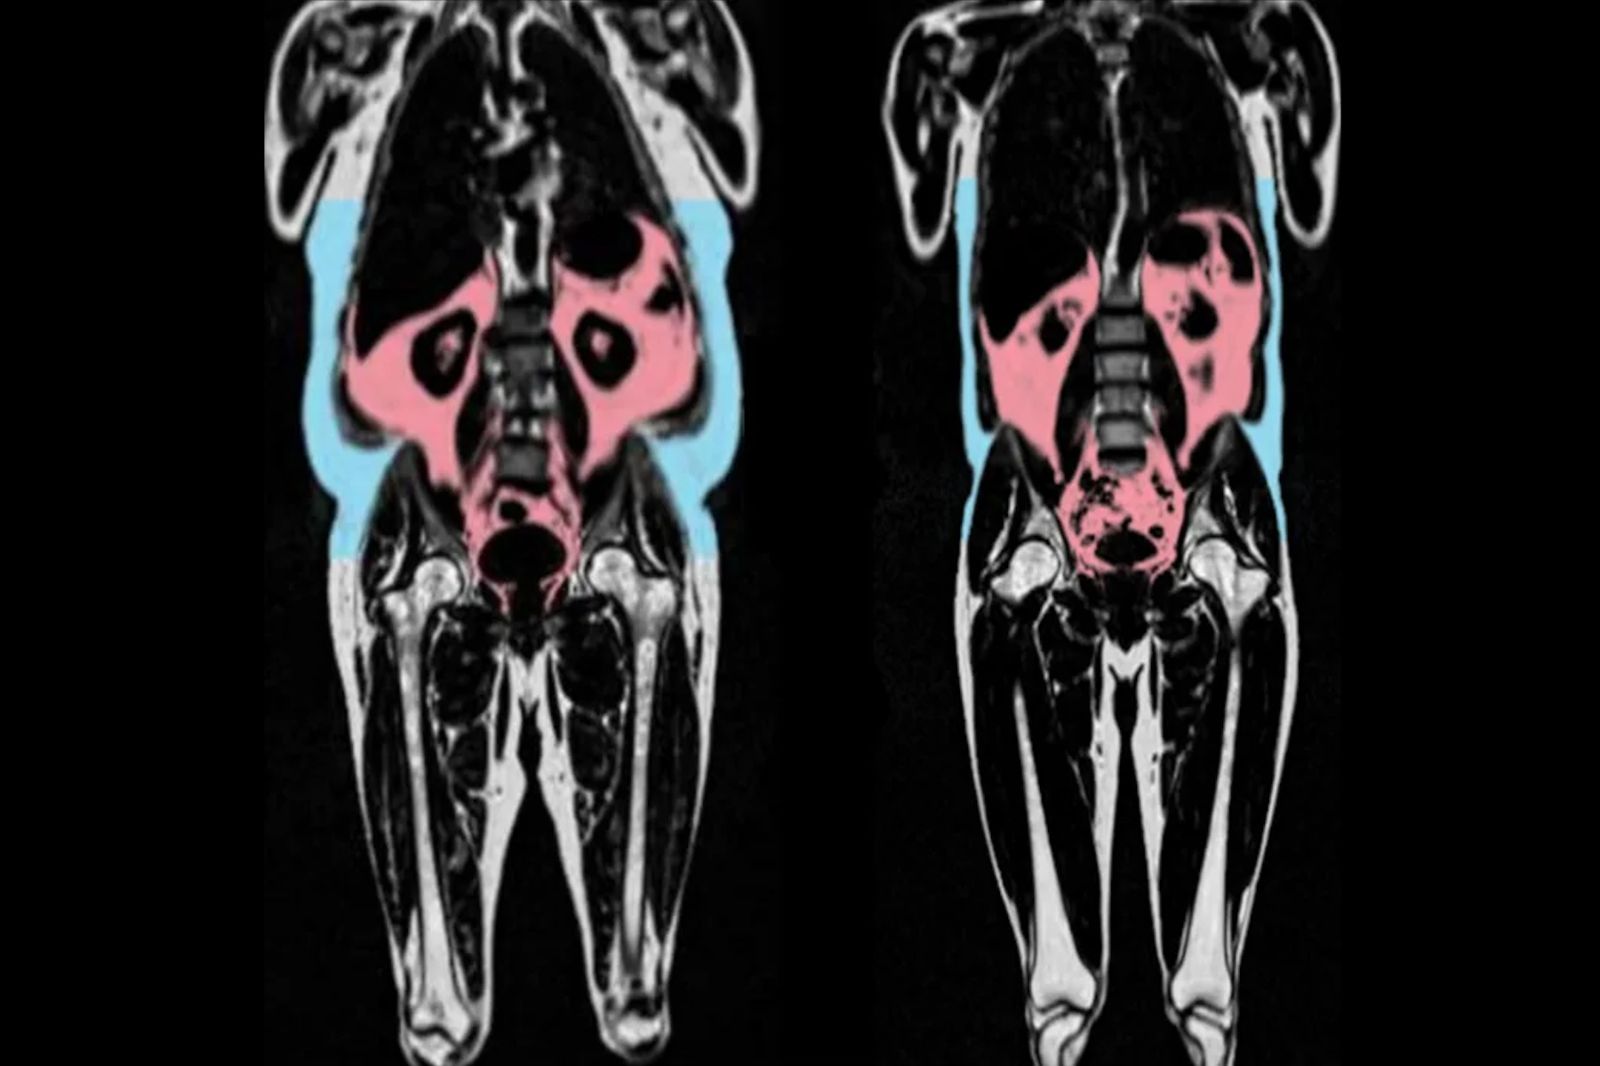

首席研究員、倫敦帝國學院教授奧裡根(Declan O'Regan)表示,研究使用核磁共振描繪出脂肪的數量與位置,同時使用AI評估心臟與血管掃描狀況,判定出衰老程度,目前得知不同體型存在著不同差異,不過目前尚未清楚得知「如何導致不良的健康結果」。

研究進一步指出,體型恐比體重更容易影響身體健康,如腹部脂肪較大,呈現「蘋果形」的男性,心臟老化速度較快。此外,臀股脂肪(臀部上方及大腿周圍)較豐厚的「梨形」女性,心臟則較為健康,甚至有助於預防心臟病、中風及第二型糖尿病。奧裡根坦言,「BMI 並不是預測心臟年齡的好方法,了解脂肪在體內儲存位置也具有重要性」。